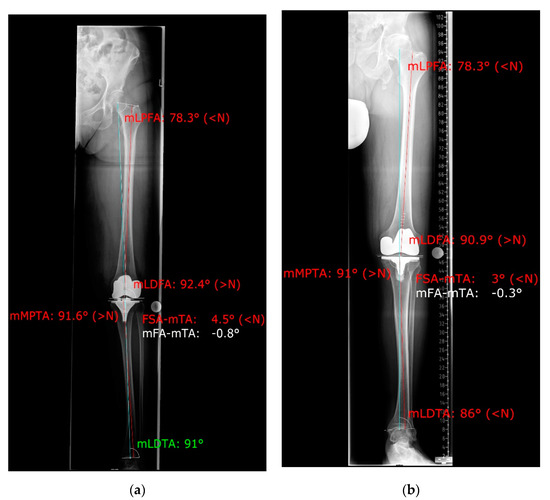

2. Materials and Methods

3.2. Coronal Alignment